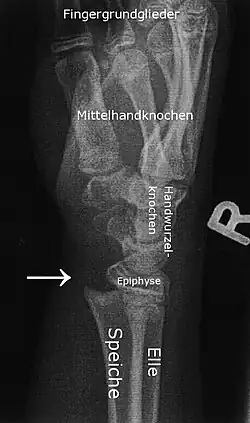

Bilderklärung

Auf dem linken Bild sieht man die frische Epiphysiolyse. Die distale (körperferne, also handgelenknahe) Epiphyse des Radius (Speiche) ist so verschoben, dass der Radius selbst nach palmar (handinnenflächenseitig) verschoben ist. Der Pfeil im Bild zeigt genau auf die Stufe, die dadurch entstanden ist.

Für den ungeübten Betrachter mag verwirrend sein, dass Speiche und Elle (Radius und Ulna) auf diesen Aufnahmen hintereinander liegen und wegen ihrer relativen Durchsichtigkeit im Röntgenbild beide sichtbar sind.